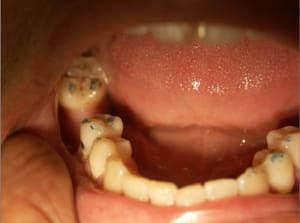

Cas_3_a_mascgd.jpg

Voir le message contenant cette image